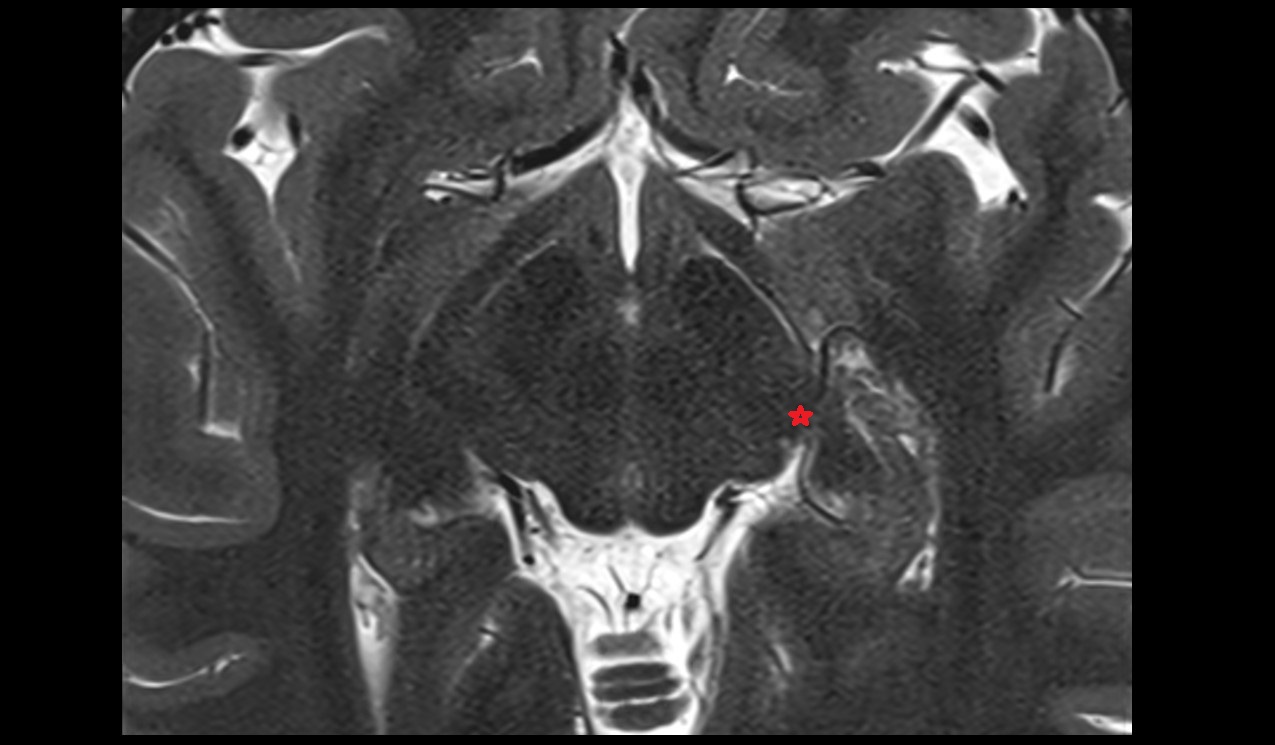

- Temporomandibular joint

- Articular disc of temporomandibular joint

- Mandibular condyle

- Mandibular fossa